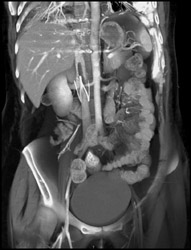

SVC Occlusion Due to Sarcoidosis